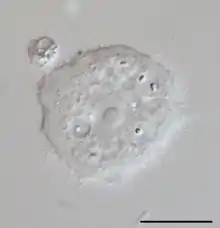

Acanthamoeba est un genre d'amibozoaires, les plus fréquents dans le sol, et aussi fréquemment trouvé dans l'eau douce et d'autres habitats. Les cellules sont petites, typiquement entre 20 et 40 μm de long en fonction des espèces, et peuvent prendre deux formes : une forme dormante, kyste ou une forme active, trophozoïte (aussi nommé végétative). Ces formes leur permettent de se mouvoir, se diviser et se nourrir plus facilement. Cet organisme peut passer d'une forme à l'autre en fonction des conditions environnementales. Si elles sont favorables à sa croissance, le trophozoïte est observé, alors qu'en cas de stress on observera un kyste. Les pseudopodes forment clairement un lobe hémisphérique antérieur, et il y a différentes courtes extensions filiformes au bord du corps. Elles lui donnent une apparence épineuse à laquelle le nom Acanthamoeba se réfère. Les kystes de la plupart des espèces d'Acanthamoeba sont habituellement de types polygonaux et sont fréquemment retrouvés. La plupart des espèces sont des prédateurs naturels des bactéries libres, mais certaines sont des parasites opportunistes qui peuvent causer des infections aux humains et autres animaux.

Les espèces d'Acanthamoeba se distinguent surtout d'après leurs kystes. Ces espèces sont divisées en 12 groupes (du T-1 à T-12), basés sur la séquence ADN du ribosome 18S. Elles incluent les suivantes (celles marquées d'un astérisque sont connues comme causant des infections):